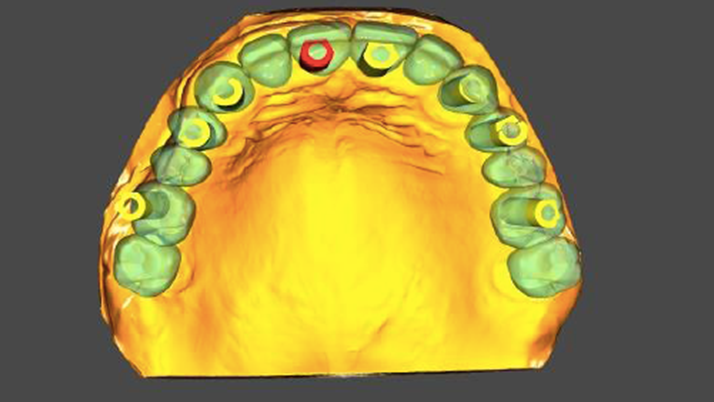

Clinical case: Extraction of all teeth in upper maxilla,

immediate implant placement, & provisionalization

- Courtesy of Dr. Iulian Filipov, Romania -

Keywords

AnyRidge, immediate placement, immediate provisionalization, maxillary fully edentulous case, initial stability, edentulous, Dr. Iulian Filipov, R2GATE, MEGA ISQ

Products:

AnyRidge implant system, Mega ISQ, R2GATE

“AnyRidge ensures long-term biological stability

& functionality even in

full-mouth rehabilitation case. ”